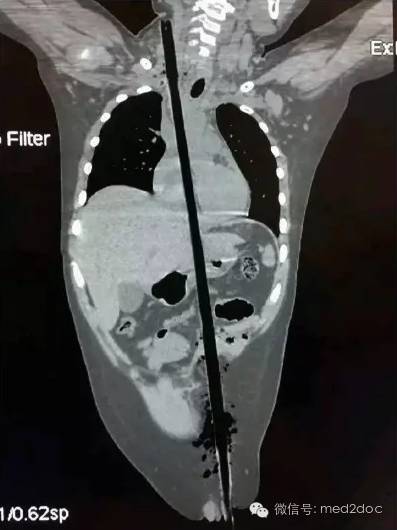

6月14日下午3点多,济南一名中年男子从5米高空坠落,地上正好有一竖起的钢筋,这根钢筋从男子的阴部直穿头顶。患者是由一根粗约1.5厘米的钢筋从阴部直插穿头顶,阴部以下露出长约四十厘米的钢筋,头顶上穿出长约五十厘米的钢筋,男子*体下**和脸部都留着鲜血,场面触目惊心。

经过CT等全方面检查后,确定钢筋已贯串男子的泌尿、腹部、胸部、口腔、鼻腔、脑部等具体部位。钢筋从男子的右阴囊插入,途径泌尿系统,伤及腹部的肝脏,紧贴颈动脉贯串而过。从咽喉直插入口腔,伤及舌头,从上颚经鼻腔,插入大脑,钢筋从头顶穿出。

术中,多科室医生合作,同时将伤者的头颅、胸腔、腹腔打开,在完全暴露的情况下取出钢筋。经过7个多小时,手术在15日凌晨1点多结束,钢筋被顺利取出,测量长度约1.5米。男子性命被保住,这也创造了医学的奇迹。